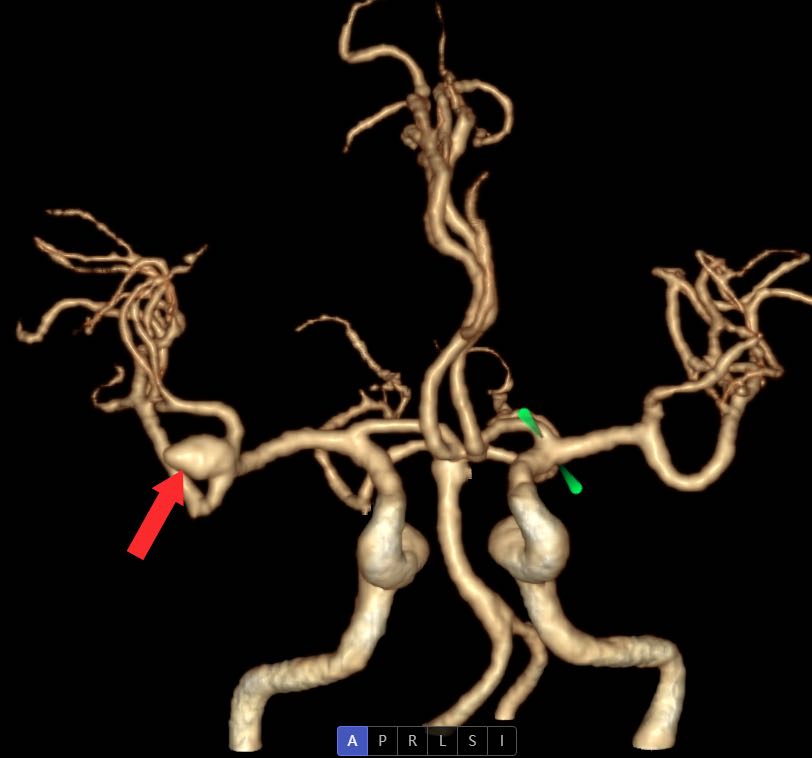

9月24日0:30左右,一场与时间赛跑的抢救正在手术室悄然进行中。9月23日22:00时许,35岁的覃女士因“突感头晕头痛,恶心呕吐”不适,家人呼叫120救护车送至深圳市中西医结合医院急诊科抢救室。急诊科救治团队迅速展开一系列抢救和检查,患者为右侧大脑中动脉动脉瘤破裂出血,病情紧急。此时,正值“桦加沙”超强台风防御期,脑外科的张力主任、朱美蓉护士长以及全体值班、备班、二线的医生,正在科室留守,以应对各种突发事件。接到急诊科抢救室会诊通知后,张力主任团队迅速响应。张力主任介绍,患者既往有高血压病史,CT检查结果有动脉瘤破裂出血,且动脉瘤较大,形态不规则,再出血风险较大,一旦再出血后果将不堪设想,需尽快进行急诊开颅手术治疗。

红色箭头处为动脉瘤。

患者家属同意手术后,9月24日0:30左右,在麻醉科和手术室的协助下,由宝安区神经外科首席专家张力主任主刀,值班医生刘裕浩副主任医师密切配合,为患者进行紧急开颅脑动脉瘤夹闭手术。经过近7个小时的努力,顺利完成手术,成功为患者摘除颅内“炸弹”。患者被送入脑外科重症监护病房进行监护治疗。目前,患者已脱离生命危险。